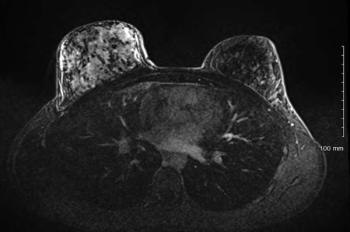

Synchronous Bilateral Lung Cancer With Discordant Histology

ByMehmet Sitki Copur, MD, FACP,Rudy P. Lackner, MD,Whitney Wedel, MD,Nikki Lintel, MD,Matthew Stritt, MD,Kalpesh Ganatra, MD Medical oncologsts discuss the case of a 70-year old woman with synchronous multiple primary lung cancer.